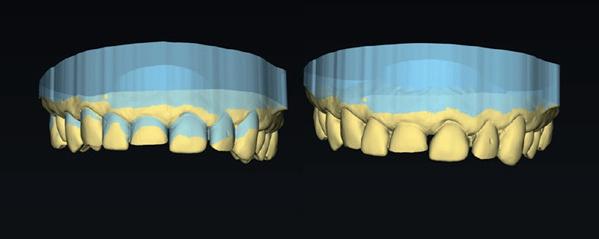

Naast een indirecte vervaardiging kunnen composietrestauraties uiteraard ook direct worden gemaakt. Een beethoogteherstel kan uit de hand worden gedaan, maar deze procedure is tijdrovend, moeilijk en mogelijk ook wat onvoorspelbaar. Wanneer het verlies aan tandweefsel kan worden aangevuld met een digitale planning kan deze op voorhand veel inzichtelijker worden gedaan. Hierbij wordt gebruik-

gemaakt van een digitale mock-up (afbeelding 4) en een transfer naar de mond. Er kunnen meerdere methodes worden gebruikt om deze overzetting van de digitale planning te bewerkstelligen. Denk hierbij aan een puttymal om bijvoorbeeld een front te verlengen. Hierbij worden allereerst palatinale shells geplaatst om hier vervolgens de directe composietrestauraties uit de hand tegenaan te zetten. Bij een injectable techniek kan worden gekozen voor een dieptrekmal over een (geprint) model van de nieuwe situatie. Omdat deze moeilijk over te zetten is zonder de elementen te verblokken, wordt er vaak voor een alternerend model gekozen, waarbij eerst de helft van de restauraties in de mock-up wordt geplaatst en deze vervolgens wordt overgezet. Daarna wordt de mock-up van de gehele nieuwe situatie middels een dieptrekmal gekopieerd, de zojuist in de eerste fase geplaatste restauraties gesepareerd met teflon en vervolgens kan de tweede set restauraties worden geplaatst.

In dit artikel wil ik laten zien hoe deze technieken in de praktijk ook kunnen worden uitgevoerd zonder gebruik te maken van gebitsmodellen. Wanneer we deze fase namelijk kunnen overslaan, maar de transfers direct zouden kunnen printen, is een dieptrekstap niet langer meer noodzakelijk. In dit geval is gekozen voor het vervaardigen van een mock-up in Inlab software van Dentsply Sirona, maar deze kan uiteraard ook in andere programma’s worden uitgevoerd. Allereerst worden de nieuwe restauraties ontworpen op de bestaande situatie. Hierbij wordt bij het aangeven van de outlines, vermeden dat deze elkaar overlappen. De parameters worden vervolgens dusdanig aangepast dat er geen noemenswaardige overgang meer tussen element en restauratie aan-

wezig is (afbeelding 5). In deze designfase moet er wel rekening worden gehouden met in te bouwen beetverhoging. Dit is mogelijk door de beet als verhoogde dimensie te scannen of door opening van de articulator in de software. De eerste is uiteraard preciezer en geniet de voorkeur. Wanneer alle elementen virtueel zijn opgebouwd, kunnen ze na exporteren in de administratieve fase alternerend in het model worden geplaatst (afbeelding 6). Wanneer dit gebeurd is, kan vanuit deze fase worden gekozen voor het printen van een model voor een dieptrekmal. In dit geval zullen we echter kiezen voor het printen van een “splint”. Wanneer we deze splint volledig laten aansluiten op het model door de uitblokking te verwijderen en de elementen tot 2-3 mm voorbij de cervicale randen te omvatten, is een goede overzetting in de mond gegarandeerd (afbeelding 7). De occlusale afsteuning is geborgd door de elementen die in deze fase nog niet worden opgebouwd en een cervicale afsluiting voorkomt een doorpersing van composietmateriaal. De te vervaardigen mal moet worden geprint in een medium flexibel materiaal. Dit zorgt voor een juiste plaatsing ervan, daar de uitblokking in de ontwerpfase van de mal is verwijderd. Daarnaast moet de mal voldoende licht doorlaten om de composiet door het materiaal initieel uit te kunnen harden. Heel belangrijk is dat het printmateriaal niet aan de composiet hecht om trekkrachten bij het verwijderen ervan te voorkomen. Er is in dit geval gekozen voor IBT Flex Resin van Formlabs. Deze kunsthars wordt na het printen gereinigd met IPA en na droging, volgens de specificaties, in een waterbad uitgehard in de lichtoven. Dit laatste voorkomt de hechting van composiet aan het materiaal. In de mal worden vervolgens handmatig per element twee kanaaltjes gemaakt. Eén om te kunnen injecteren en